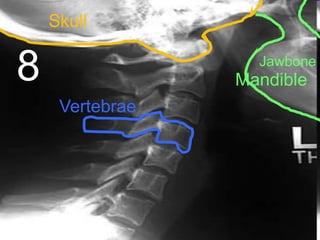

Skull

8

Jawbone

Mandible

Vertebrae